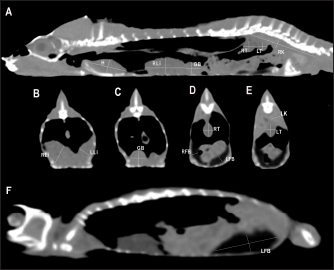

Heart, liver, including caudal vena cava (CVC), hepatic vessels, and gallbladder, esophagus, stomach, intestines, cloaca, gonads, fat bodies, kidneys, and when distended, urinary bladder were identified in the CT images with the aid of the anatomical sections (Fig. 4). The spleen, pancreas, and adrenal glands could not be identified. Measurement values of the liver, testes, fat bodies, and kidneys observed in CT in veiled and panther chameleons are seen in Table 1.

Fig. 4. Sagittal precontrast CT image displayed in soft tissue window (A) and transverse cross-sectional views of gross anatomical sections at the level of the liver (B), gallbladder (C), fat bodies (D), and kidneys (E) in a veiled chameleon (C. calyptratus). The right of the patient is on the left of the image. H, heart; RLu, right lung; LLu, left lung; Es, Esophagus; RLi, right liver lobe; LLi, left liver lobe; ST, stomach; GB, gallbladder; RK, right kidney; LK, left kidney; RT, right testicle; LT, left testicle; RFB, right fat body; LFB, left fat body; Co, colon.